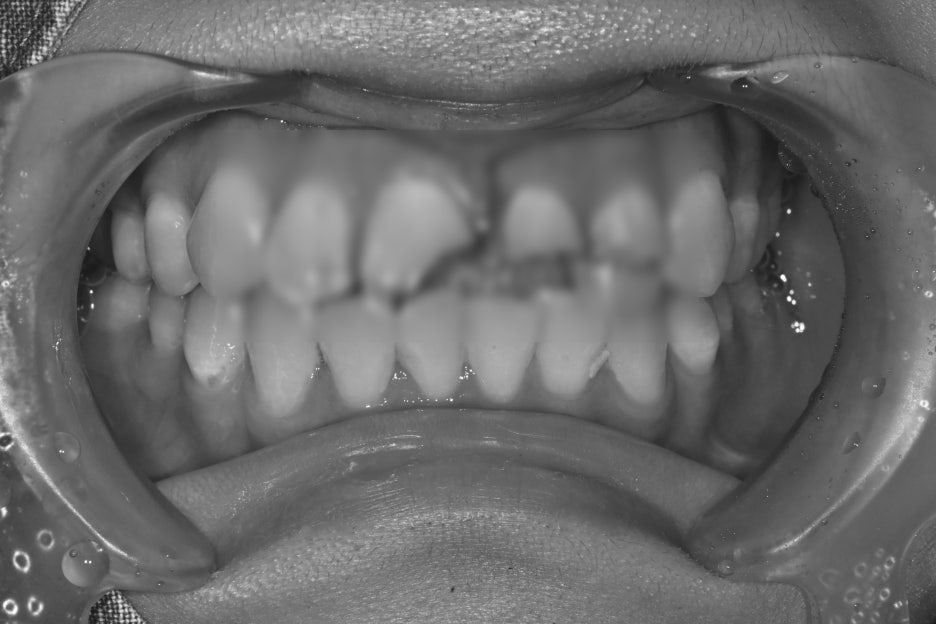

Before and after treatment photos

Photos before and after treatment

After treatment, the patient said,

“Now my front teeth are aligned again, so I feel more confident when smiling,”

and expressed satisfaction.

She also felt more reassured because people around her said it looked natural.